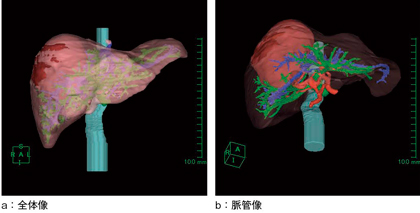

図2 3D画像

肝実質の透過性を調節することで,腫瘍の肝内での位置関係の把握が容易となる。肝動脈と門脈の関係も位置のズレがなく正確に表示できている。